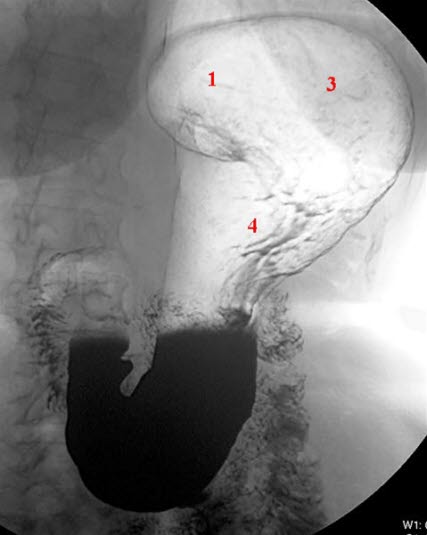

Magesekken vist med dobbelkontrast-teknikk med barium og luft hos stående pasient

- Cardia

- Nummeret mangler

- Fundus

- Corpus